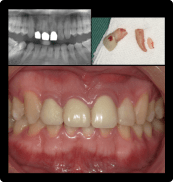

昔ぶつけた歯が揺れている

BEFORE

AFTER

症例概要

年代・性別

50歳代 女性

主訴

前歯を綺麗に治したい

治療内容

上顎両側1番CADCAM冠(根管治療)、上顎右側2番インプラント治療(抜歯即時インプラント)

治療期間

4ヶ月

治療のリスク

骨が少ない場合や膿の大きさが大きい場合は同時にできない場合があります。

治療費用

506,000円(税込)